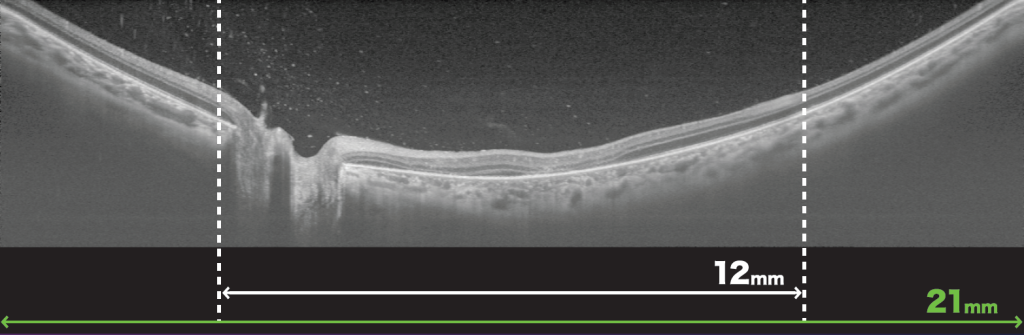

かんたんに取り付けられるアタッチメントレンズで、最大スキャン幅21㎜の広角OCT撮影が可能となり、多彩な検査ルーチンに対応できます。

Triton Proシリーズは、「広角OCT撮影用アタッチメントレンズ WA-1」(別売)最大21mmのラインスキャン、ラジアルスキャン、OCT-Aデータが取得可能になりました。さらに、IMAGEnet6ソフトウェアにはSmart Denoise機能が追加され、トプコン独自のノイズ除去機能により、3Dを含むB-scanおよびOCT-A*4画像がより鮮明に描写可能です。さらに、角膜隅角エリアにも解析機能を追加しました。